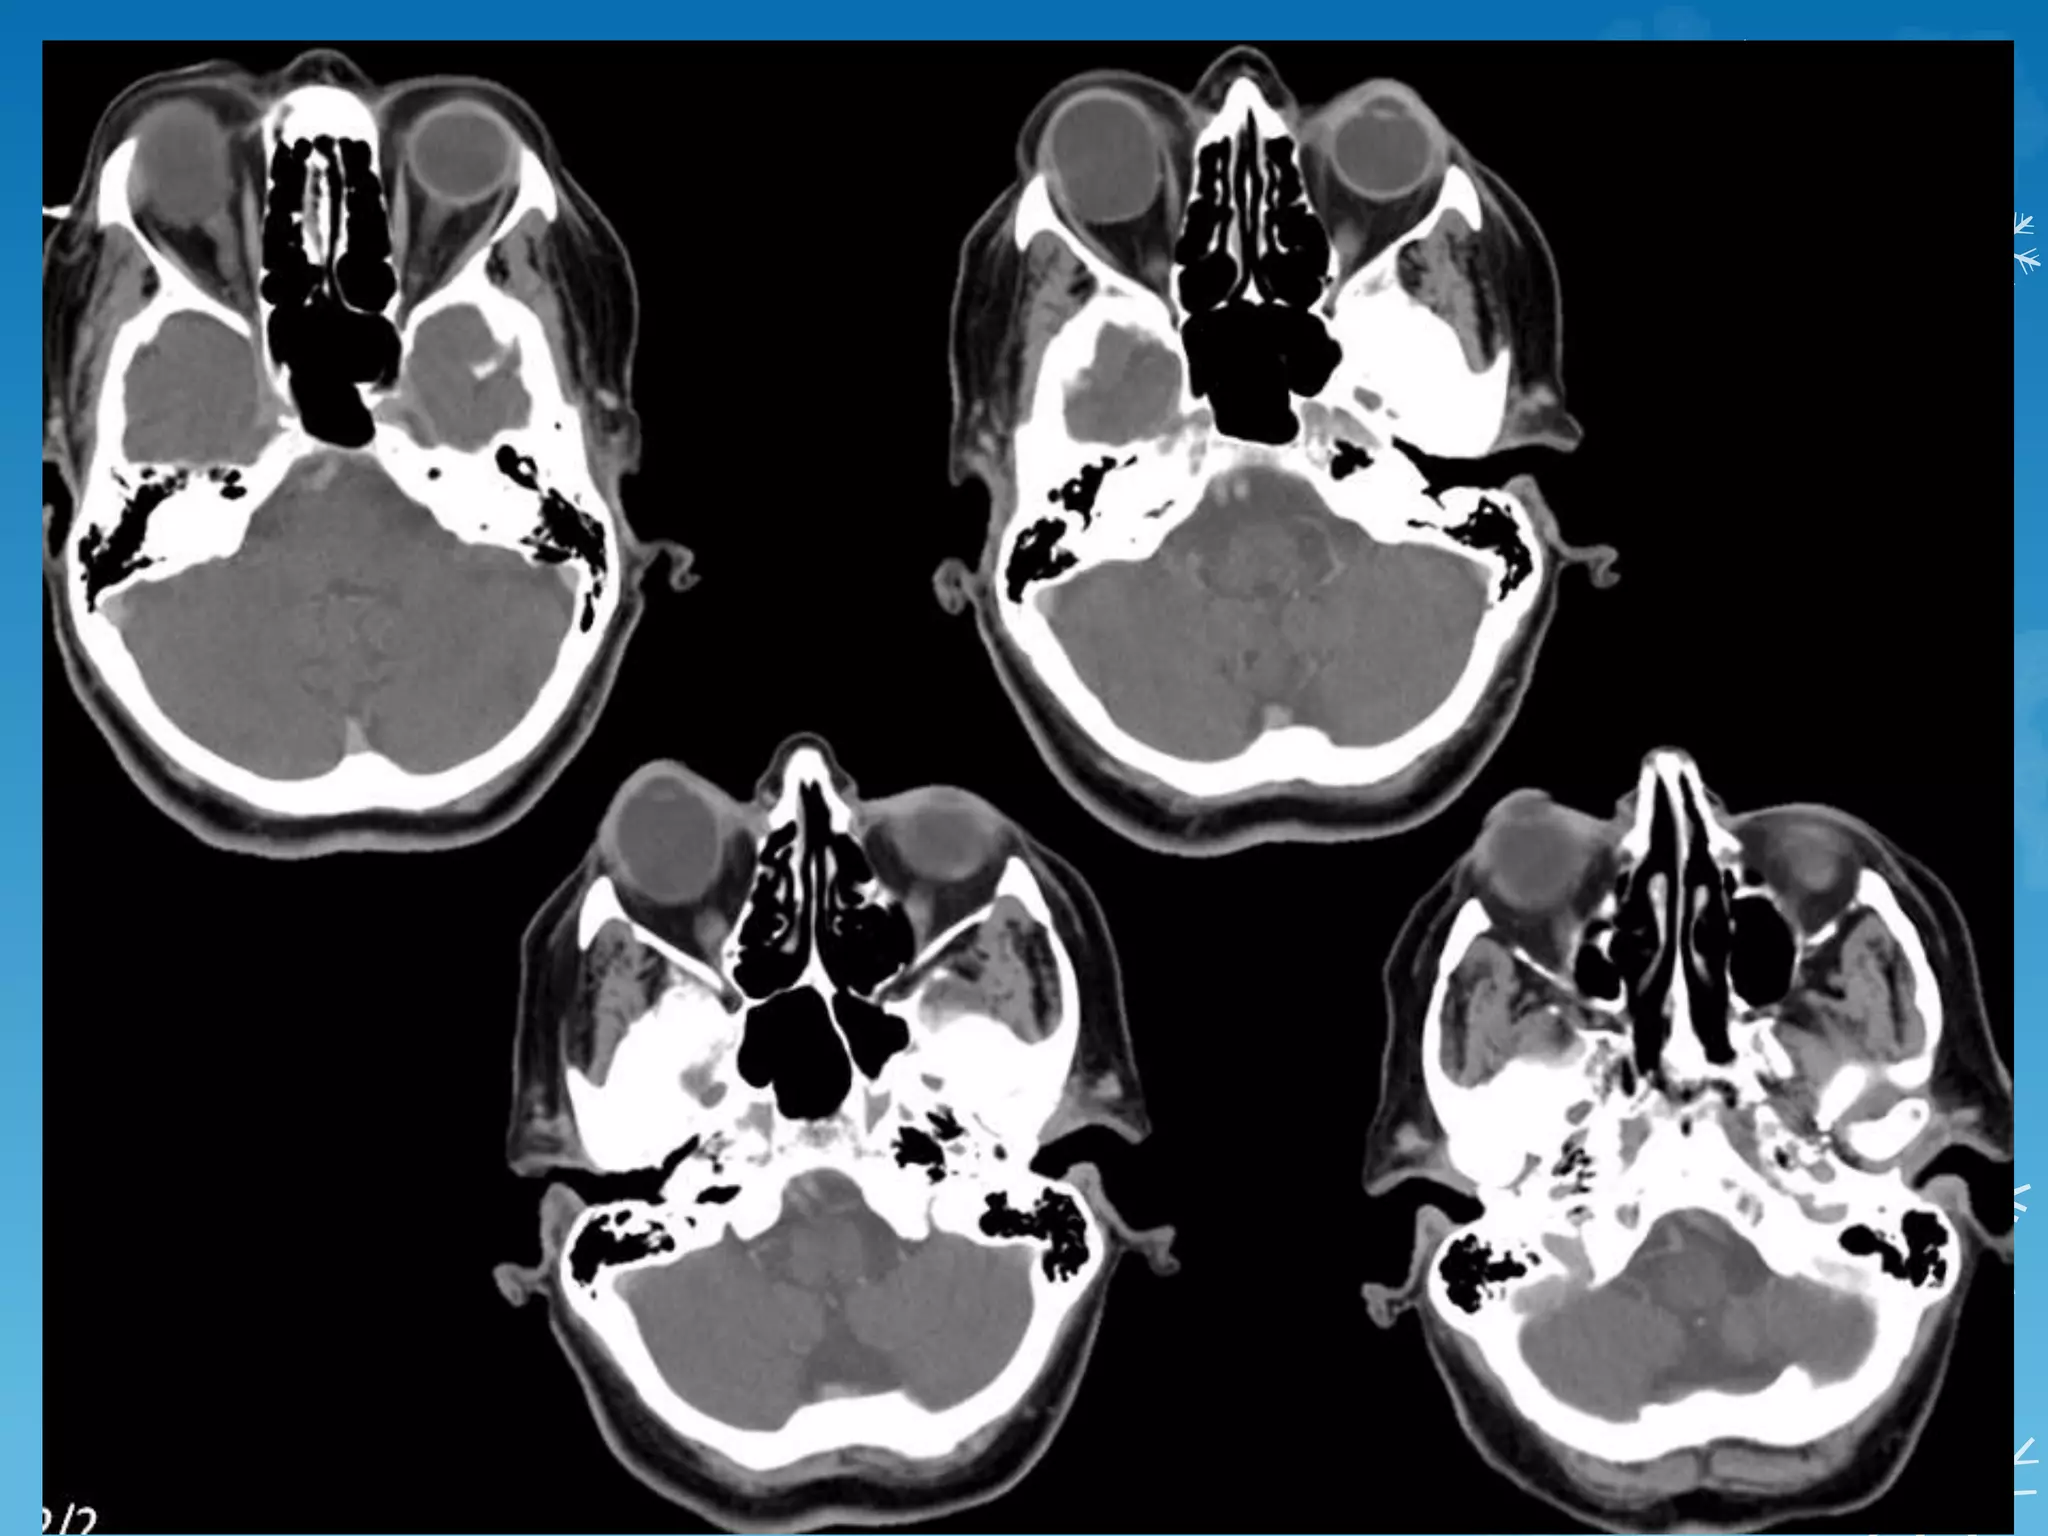

A 7-year-old boy presents with repeated transient ischemic attacks.

Moyamoya Disease